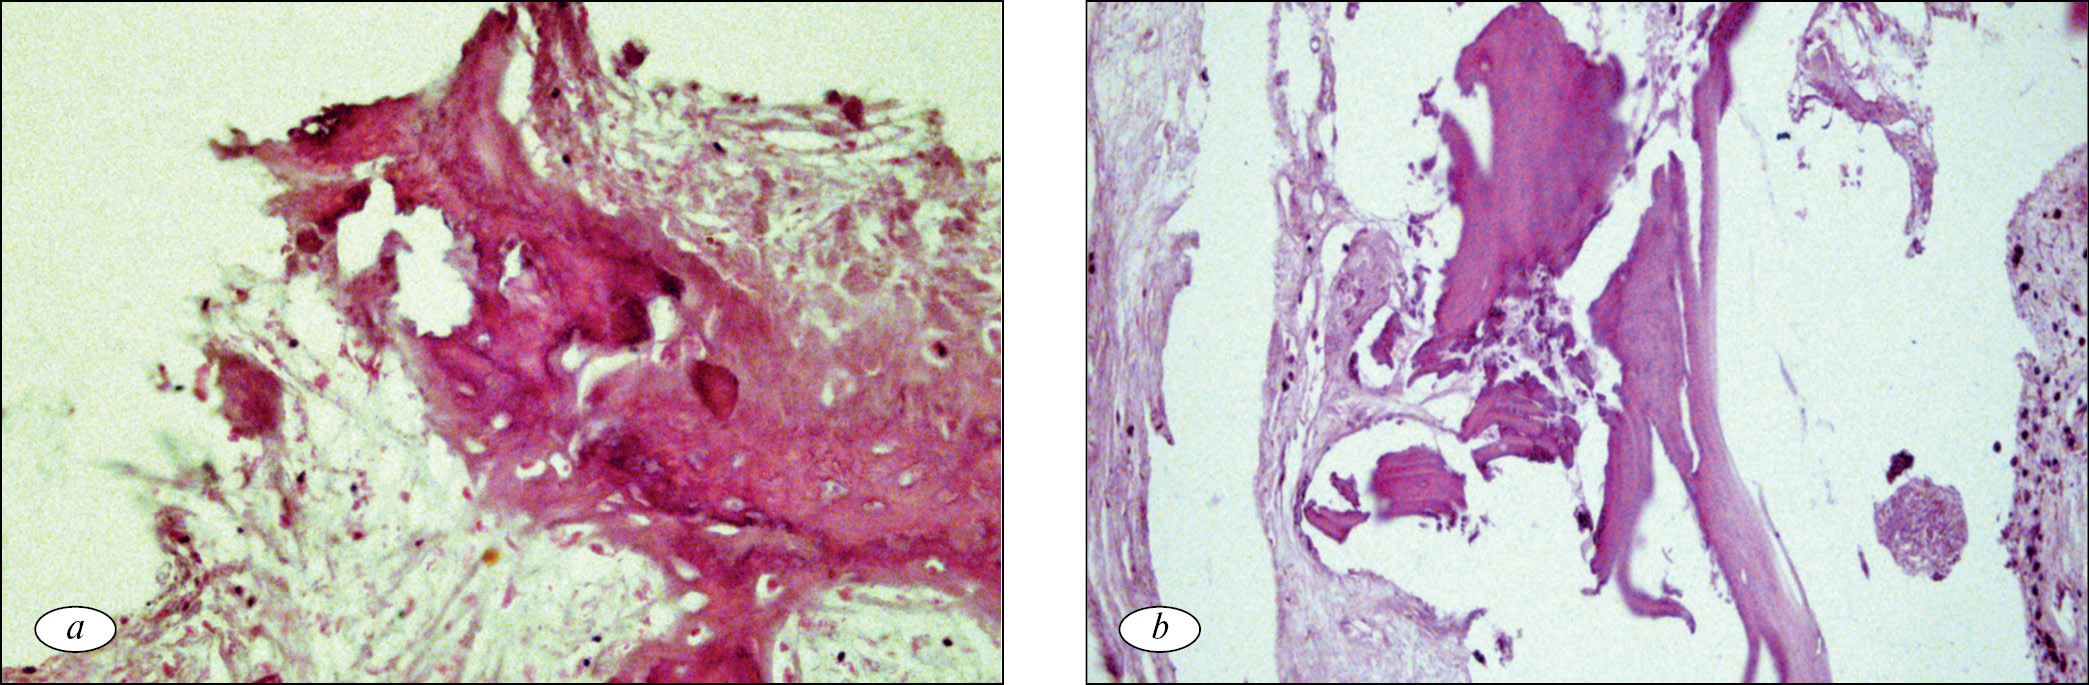

В результате патогистологического исследования фрагментов костной и мягких тканей, изъятых из зоны переломов, были выявлены морфологические признаки структурной дезорганизации костной ткани в зоне перелома, различные варианты репарации костной ткани, а также реактивные изменения со стороны окружающих мягких тканей. Структурная дезорганизация костной ткани проявлялась в недостаточной минерализации костной ткани, в деструкции костных балок с развитием очаговых признаков остеолиза. Так, на фоне признаков неравномерно выраженного отека, полнокровия и разволокнения основного вещества выявлялись признаки деструкции костной ткани с образованием очаговых скоплений мелких фрагментов разрушенных костных балок (рис. 1, а) и пазушного остеолиза с образованием полостей с неровными контурами в толще костной ткани (рис. 1, b).

Рис. 1. Деструктивные изменения костной ткани в зоне перипротезных переломов бедренного компонента: а — разрушенные костные балки с очаговыми скоплениями мелких костных обломков; b — пазушный остеолиз в зоне оссификации хрящевой ткани. Окраска гематоксилином и эозином. Увел. ×160

Fig. 1. Destructive changes in periprosthetic fractures bone tissue of the femoral component: a — destroyed bone beams with focal accumulations of small bone fragments; b — axillary osteolysis in cartilage ossification fabrics. Staining with hematoxylin and eosin. Magnification × 160